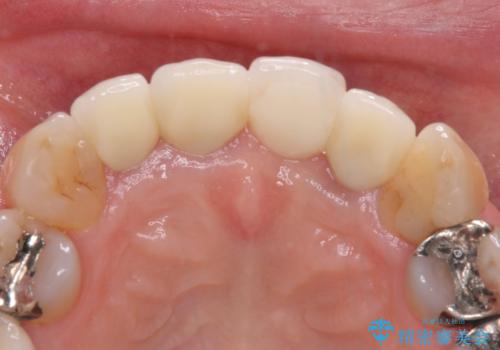

1. 折れてしまった前歯 インプラントによる補綴治療の治療前

3. 折れてしまった前歯 インプラントによる補綴治療の治療後